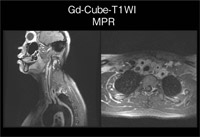

Cubeは血管のflow voidが非常に強く出るため、Black Blood法として使うことができる。高安病疑い(図3と同一症例)の造影後のCubeによるT1強調像(図7)では、動脈内・静脈内がBlack Bloodになっていて、血管壁が非常に評価しやすい画像が得られている。矢状断のほかに、横断像や冠状断像、MPR像を作ることも可能である。flow voidがきれいに出るVolum撮像法をT1強調像で使えるCubeは、将来的に期待できる技術である。

図7

図7 Cube(図3と同一症例)